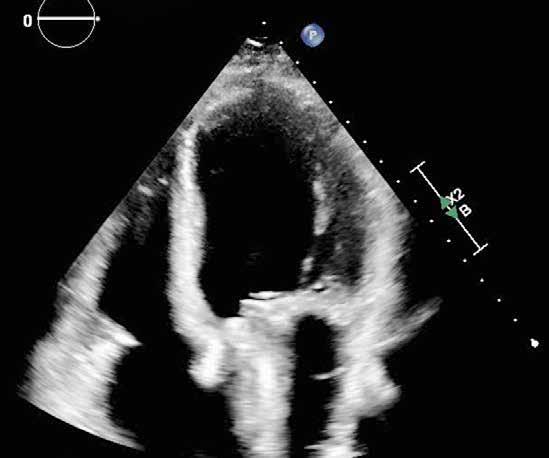

Out of BCR-ABL negative myeloproliferative neoplasm (MPNPh-) patients, 3%–14% display a concomitant monoclonal gammopathy (MGUS).1, 2 The diagnosis of MPN proceeds lymphoproliferative disease (LPD) occurrence in about 50% of patients. The median time between the diagnosis of MPNPh- and LPD was established at 72 months.3 Herein, we present an unusual outcome of low risk essential thrombocythemia (ET), diagnosed in 2008 in a 50-year-old woman. Initially, she was treated with hydroxyurea (HC) 1.5 g/daily orally. Her medical history revealed mitral and aortal valve insufficiency, which was diagnosed in 2018, and the episode of transient ischaemic attack (2018), resulting in foci cerebral ischaemia (MRI). In 2019, due to toxicity, the HC treatment was stopped. The therapy with the pegylated interferonα 2a (Pegasys, PEG-INFα2a) was started in August 2020. The molecular work-up showed no JAK2 V617F and MPL exon 10 mutation and the presence of the type 2 CALR mutationLRG_828t1:c.1154_1155insTTGTC, LRG_828p1:p.(Lys385Asnfs*47)

(VAF 35%). The bone marrow (BM) biopsy performed in 2020 showed the normocellular BM, locally hypercellular, with an erythroid/ granulocytic cell ratio of 1:3, and normal erythroid and granulocytic proliferation index and maturation pattern. The blast cell (CD34+, CD117+) content was determined at 1%–2% of nuclear cells. An increased number of mediumsized and large megakaryocytes (factor VIII+) was found, without the tendency to form clusters (locally forming loose clusters consisting of 4–8 cells). The BM fibrosis (MF) grade according to the European consensus criteria was 0/1.

In September 2021, she experienced a fracture of the L1 vertebrae of the spine which was treated with Th12-L1 stabilization with laminectomy. The PETCT scan revealed multiple osteolytic lesions in the bones.

Immunofixation studies showed the IgG kappa monoclonal protein in the blood at the concentration of 49.6 g/L. The WBS performed in January 2022 documented the fracture of Th9, the presence of an intramedullary tumour in the bottom part of the stern. The MFC of the BM cells showed 65% of abnormal plasma cells. The repeated biopsy documented BM cellularity 60% with about 30% of dispersed plasma cells, locally forming infiltrates. Erythroid cell line content e-cadherin+ was determined at 30%. The granulocytic cell [CD15+, MPO+] line and megakaryocyte (factor VIII+, CD61+) evaluation showed a normal morphology and maturation pattern. MF +1. Retrospective analysis of a biopsy sample collected in 2020 (before PEG-INFα2a treatment initiation) confirmed the presence of a small, abnormal plasma cell population with the same immunophenotypic characteristic (Figure 1).